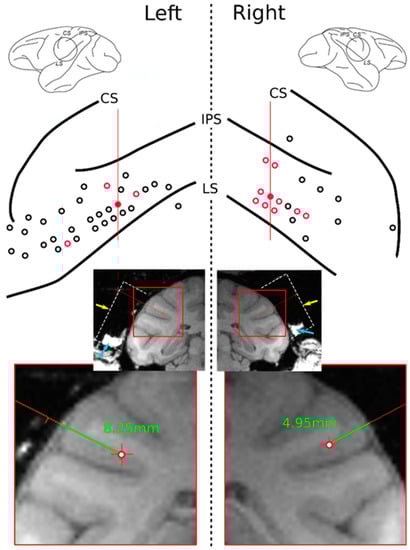

2.3. Data Acquisition and Recording Sites